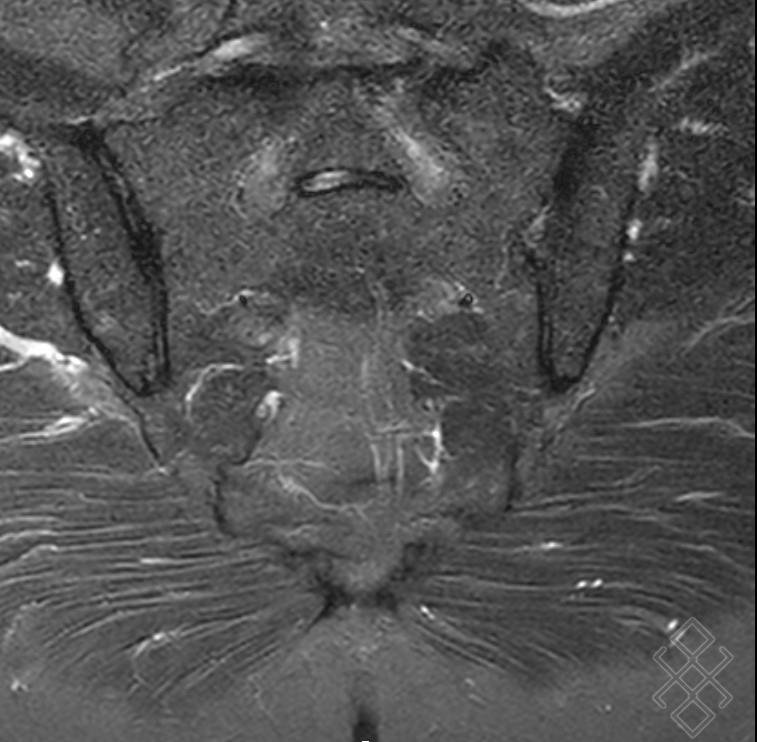

Cet examen est indiqué essentiellement dans la recherche d'une inflammation aigue ou chronique de cette articulation, appelée sacro illite. Définition, position, structure, rôles, pathologies, diagnostic et traitements

Sacroiliite droite. Sclérose souschondrale (bande hypointense). IRM,... Download Scientific. IRM du bassin avec atteinte dégénérative et inflammatoire des sacro iliaques Le positionnement de l'aiguille est en effet délicat et il est fréquent que l'injection ne soit.